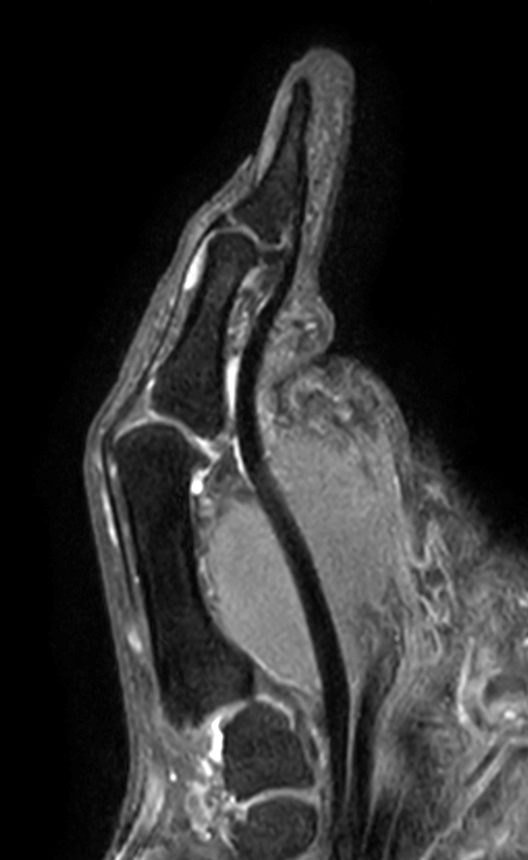

Patient with pathology on the thumb. ExamCard includes mDIXON XD TSE to achieve uniform, complete and consistent fat-free imaging. It simplifies the scan procedure by providing multiple image types in one single scan, including with/without fat suppression contrasts.

Sagittal T1w TSE